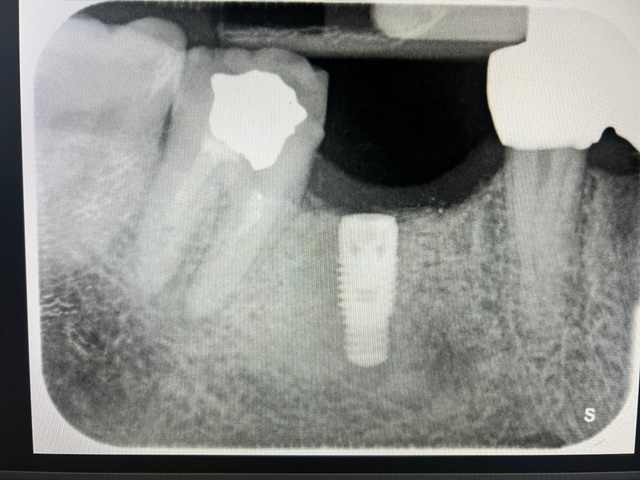

CASI IMPLANTOLOGIA DENTALE

CASO 2